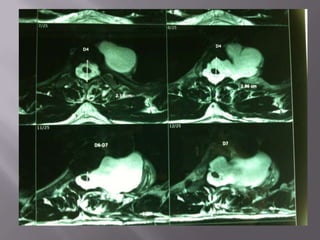

 This coronal T1-weighted, spin-echo image demonstrates the tumour well and shows

that it does not enter the spinal canal or encroach significantly on the adjacent foramina.

 This coronalT1-weighted, spin-echo image demonstrates the tumour well and shows that it does not enter the spinal canal or encroach significantly on the adjacent foramina. P

 MRI - Variable T1-weighted signal intensity that

may be similar to spinal cord.

- high signal intensity peripherally and low

signal intensity centrally (target sign) on T2-W.

- 10% may extend appear as dumb-bell-shaped

masses with widening of the affected neural

foramen.

 IMAGING -The rib spaces and the intervertebral foramina may be widened by the tumour.  CT - homogeneous or heterogeneous enhancement after intravenous contrast medium. Punctate foci of calcification may be seen.  MRI - Variable T1-weighted signal intensity that may be similar to spinal cord. - high signal intensity peripherally and low signal intensity centrally (target sign) on T2-W. - 10% may extend appear as dumb-bell-shaped masses with widening of the affected neural foramen.